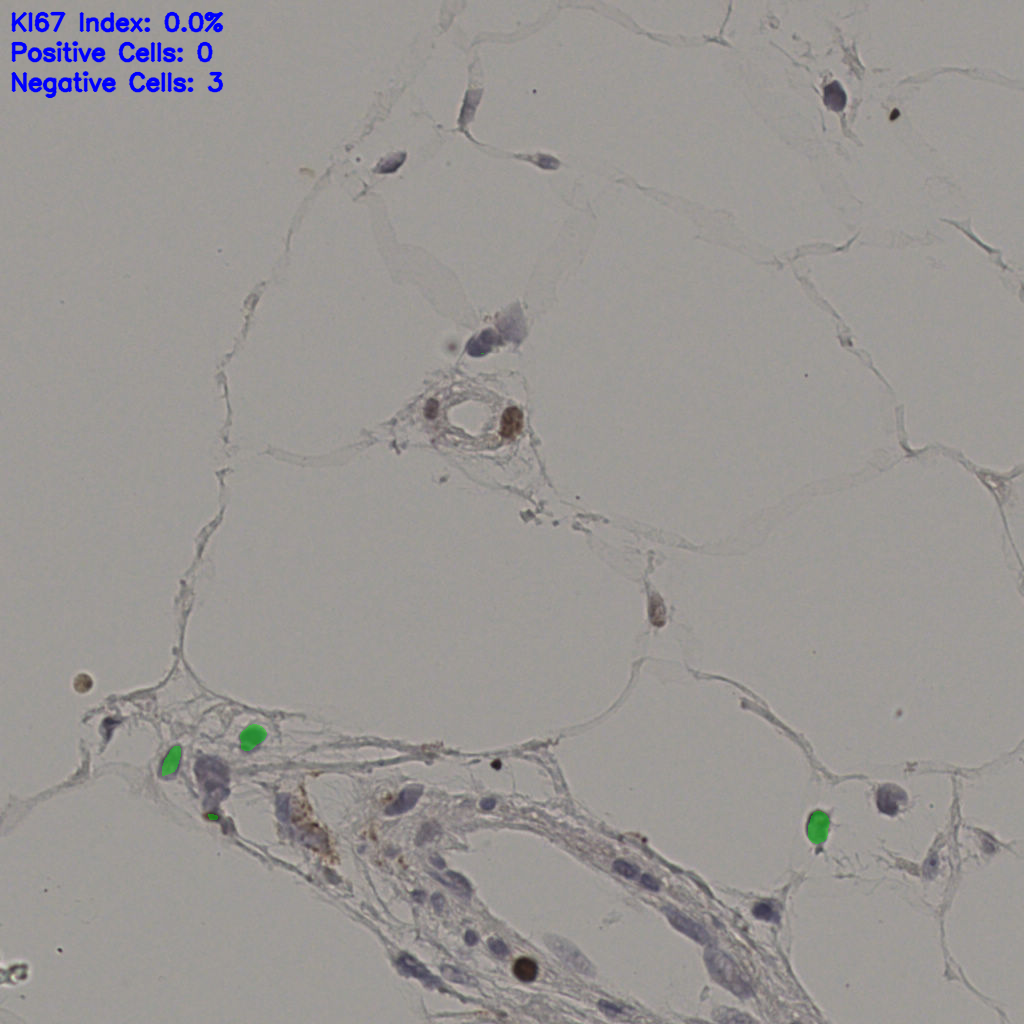

17.75%

Ki67 指数

阴 7986

阳 1723

切片统计

总切片

2640

有效

412

已标记

有效率

16%